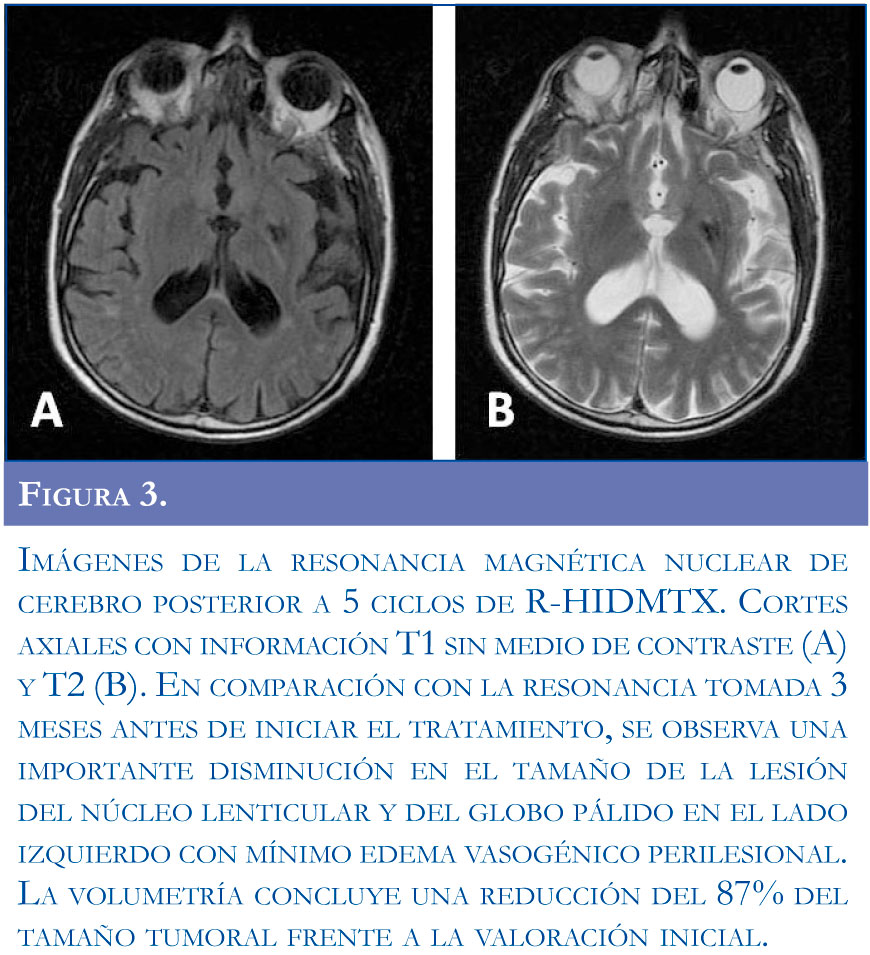

Engineer Team : RESONANCIA MAGNETICA Magnetic Resonance Imaging – Clinical Images Hallazgos por resonancia magnética cerebral de nuestro paciente. M, 21 … Imágenes por resonancia magnética anormales como predictoras de mal … Imágenes por resonancia magnética anormales como predictoras de mal … Lesiones en resonancia magnética (RM) del encéfalo y la médula espinal … Pin en Resonancia Magnética del Encéfalo A) Resonancia magnética cerebral (RMC) mostrando infartos en … Caso 1: Edema cerebral visualizado mediante RM. (A) Secuencia T1 plano … Rascacielos dormir pasta tac y resonancia diferencias retrasar … Pin on Apuntes de Enfermería y T.C.A.E Resonancia magnética cerebral secuencia T2, que muestra lesión … Meningitis aguda en la enfermedad de Behçet | Reumatología Clínica Resonancia magnética coronal normal del cerebro Fotografía de stock – Alamy Imágenes de resonancia magnética, la imagen de la cabeza en diferentes … Resonancia magnética cerebral A) protocolo T1 sagital (Caso 1). Se … Resonancia magnética cerebral. Secuencia T1 corte sagital. Atrofia … Resonancia magnética de cerebro, cortes axiales, secuencias T2. Señal … Resonancia magnética de cráneo. A y B) Cortes axiales FLAIR … Resonancia magnética (RM) de cerebro, corte axial ponderado en T2: la … RM cerebral: Interpretación paso a paso | Kenhub Resonancia magnética de cerebro, cortes axiales, secuencias T2. Señal … De Resonancia Magnética De Cerebro Foto de archivo – Imagen de arteria … Top 107+ Imagenes de resonancia cerebral normal – Destinomexico.mx -Imagen por resonancia magnética del cerebro. a) Cortes sagital y axial … resonanCia magnétiCa Cerebral donde se observa hiperintensidad a nivel … MRI (Imagen de resonancia magnética) – Tomografía computarizada de la … Meningioma – NCI Imágenes por resonancia magnética coloreadas del cerebro sano del … Resonancia magnética cerebral en secuencia FLAIR, que muestra lesiones … Contraste resonancia magnetica cerebral – senturinthegreen Relación de los espacios de Virchow-Robin con la enfermedad de … Gliomatosis cerebral – Instituto Nacional del Cáncer Pin en Neurology. Recomendaciones para la utilización e interpretación de los estudios de … Fotografía De La Proyección De Imagen De Resonancia Magnética Del … atmósfera Dirigir Cumplir anatomia resonancia magnetica Desarrollar … Pin en #MEDICINA,#SALUD Resonancia magnética de la nasofaringe De Resonancia Magnética De Cerebro Foto de archivo – Imagen de polilla … Atrofia cortical global de predominio parietal en la Resonancia … Resonancia magnética cerebral | Download Scientific Diagram Neuroblog: Resonancia magnética cerebral en la trombosis crónica de … De Resonancia Magnética De Cerebro Imagen de archivo – Imagen de … ¿Cuáles son los riesgos de la resonancia magnética? – Integra Salud … Resonancia magnética cerebral al decimocuarto día de ingreso: área … Resonancia magnética. Corte axial mostrando área infartada en el … Resonancia magnética cerebral del paciente AV evidenciando lesiones en … -Ressonância magnética de encéfalo mostrando múltiplas imagens … Resonancia magnética cerebral secuencia FLAIR (Fluid Attenuated … Resonancia magnética cerebral con protocolo de epilepsia, en sección … Resonancia magnética cerebral en corte sagital. Se observa una evidente … Resonancia magnética craneal en la que se evidencian lesiones … Logran visualizar el cerebro a detalle más completo tras una resonancia … Así decide el cerebro la severidad de un castigo De Resonancia Magnética De Cerebro, Imagen de archivo – Imagen de … A) Resonancia magnética cerebral; Secuencia Tof: oclusión de arteria … Un estudio asocia la ansiedad con la aparición rápida del Alzheimer IMÁGENES DE 18 F-PR04.MZ PET FUSIONADA CON RESONANCIA MAGNÉTICA … Imágenes por resonancia magnética anormales como predictoras de mal … Tumores de la región pineal – Instituto Nacional del Cáncer Epilepsia: una historia de voces y fantasmas | Neurología Contribución de las imágenes de resonancia magnética por tensor de … Resonancia magnética secuencia T2 plano coronal de quiste epidermoide … Resonancia Magnética Cerebral del paciente: a. Aumento de… | Download … Resonancia magnética cerebral 2022 Síndrome de hemiconvulsión-hemiplejía-epilepsia. Seguimiento de un caso … Enfoque Radiologico: La resonancia magnética permite detectar lesiones … Resonancia magnética craneal T1 con contraste que muestra angiomatosis … guidewiz – Blog Resonancia magnética cerebral, secuencia SWI. Ribete hipointenso en la … resonAnCiA mAgnétiCA de ColumnA Con gAdolinio. Corte sAgitAl en t1 de … SEMANA 12: FUNDAMENTOS DE RESONANCIA MAGNÉTICA NUCLEAR. INDICACIONES Y … DIAGNÓSTICO DE ESCLEROSIS MÚLTIP Magnetic resonance imaging of the brain – Alchetron, the free social … Resonancia magnética de órbitas | Instituto Radiológico Dr. E Castillo Alteración de la marcha en un paciente post-trasplante hepático Resonancia magnética cerebral de un paciente sano (Ay B) y paciente que … Utilidad de la resonancia magnética craneal para el diagnóstico de la … Resonancia Magnética Del Cerebro El Tumor Cerebral Foto de stock y más … De Resonancia Magnética De Cerebro Imagen de archivo – Imagen de … ABDALLA RADIOLOGIA: NEURINOMA ACUSTICO Atrofia cortical global de predominio parietal en la Resonancia … Resonancia Magnética : Producción de la imagen MRI Brain Scan — Stock Photo © Bunyos30 #18724051 Mri (imagen de resonancia magnética) Monitor con imagen de captura de … Tomografía computarizada vs resonancia magnética: diferencia y … Tumores Cerebrales – Unidad de Neurocirugía RGS Resonancia magnética de la columna, sección sagital. Observe los discos … La resonancia magnética, una técnica imprescindible en el diagnóstico … Perfusión Cerebral por Resonancia Magnética | ¿Qué es? ¿Necesita Contraste? Resonancia Magnética Cerebro A: resonancia magnética, T2 coronal preoperatoria; se observa lesión en … Resonancia magnética cerebral — Foto de stock © Bunyos30 #27340623 La resonancia magnética se perfila como detector de mentiras | Futuro … Resonancia magnética cerebral en T1 con gadolinio, cortes axial (a … MRI brain : show brain tumor at right parietal lobe of cerebrum — Stock … NEUROIMÁGENES EN ENFERMEDAD DE PARKINSON: ROL DE LA RESONANCIA …